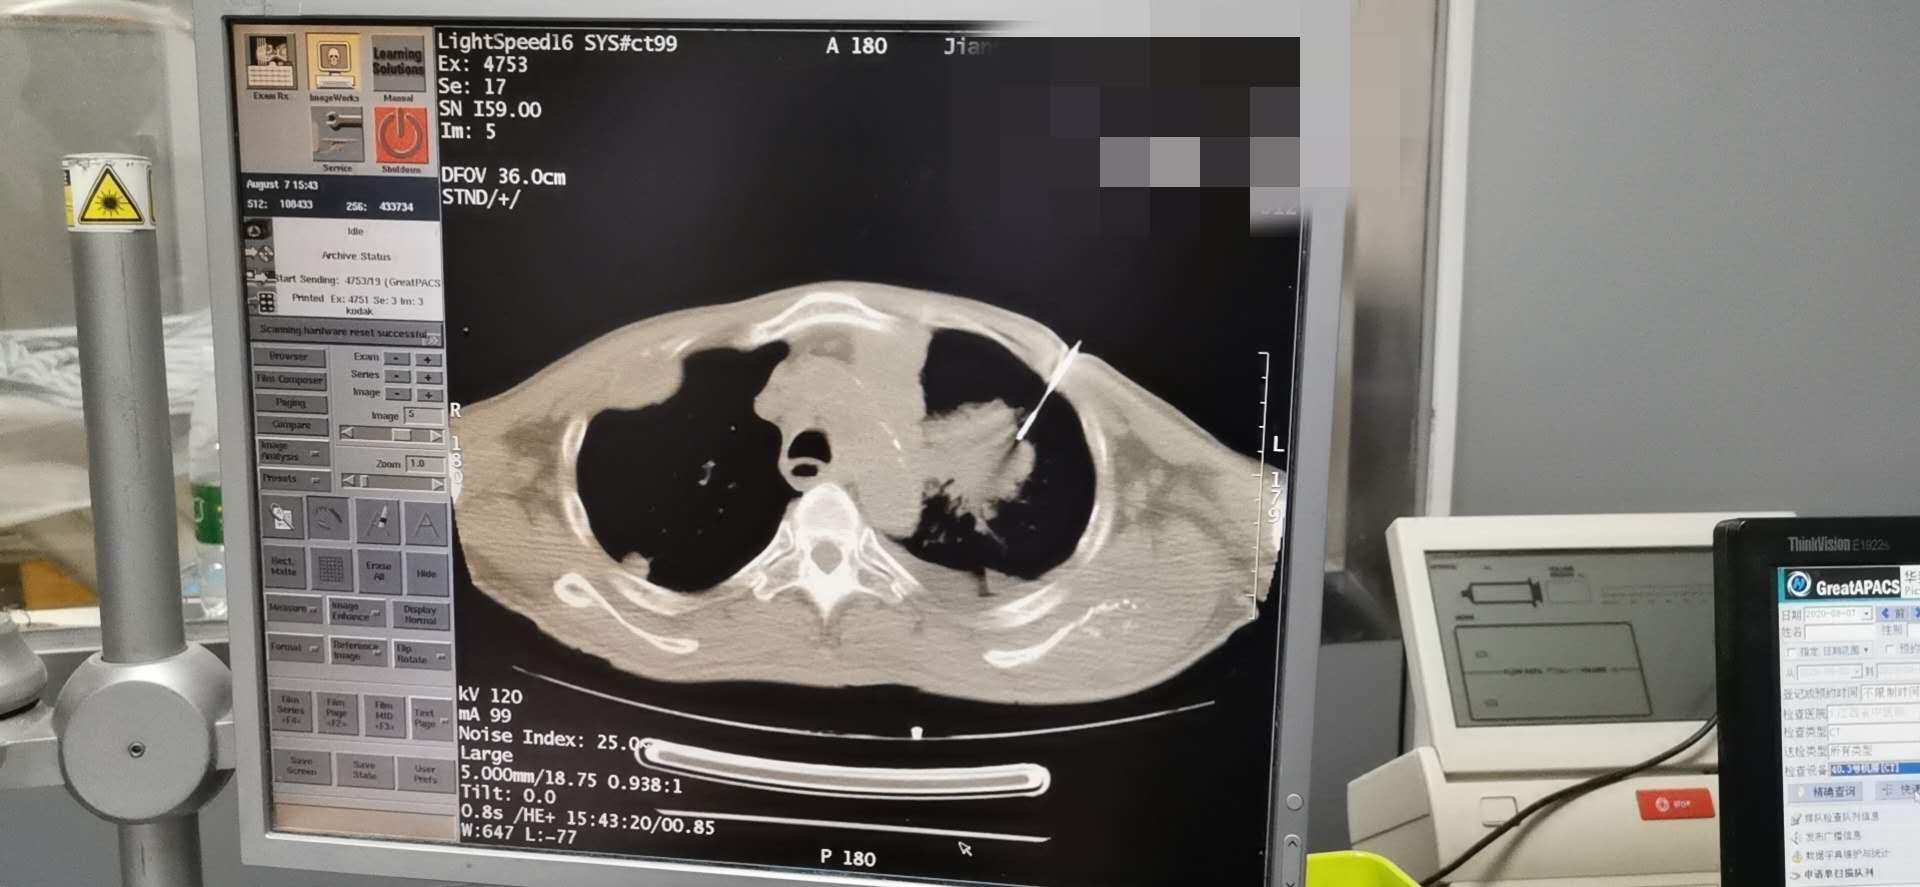

消融术中

消融术

完成高难度肺肿瘤消融术

我科成功开展一例高难度肝癌肺转移瘤消融术